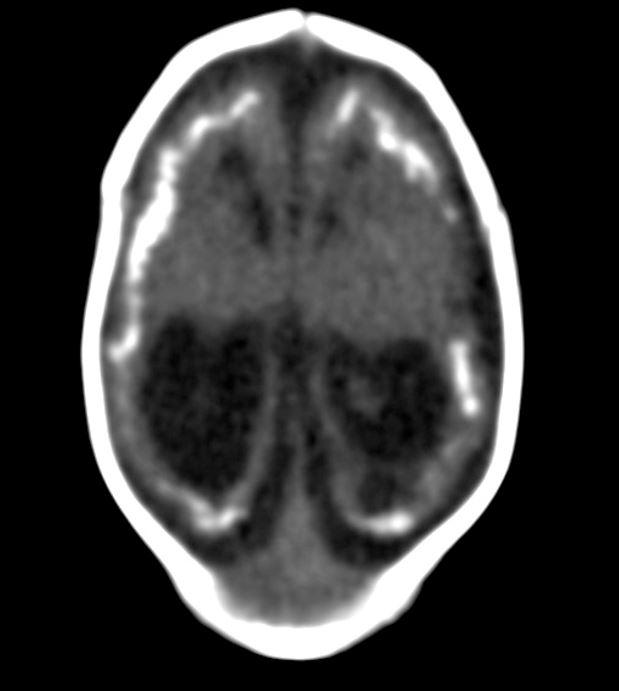

The first study looks at CT findings of the central nervous system in 16 newborn babies with congenital Zika virus infection confirmed by tests in cerebral spinal fluid.

The researchers identified a pattern of CT brain findings in the babies, including decreased brain volume, simplified gyral pattern, calcifications, ventricular dilatation and prominent occipital bone.

"We live in Pernambuco, a state in northeastern Brazil, which had the highest number of patients with microcephaly during the Zika outbreak in our country," said study author Natacha Calheiros de Lima Petribu, M.D., from the Department of Radiology at Barão de Lucena Hospital. "Our study proves that Zika virus infection can cause congenital brain damage in babies with and without microcephaly."